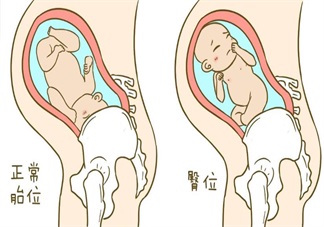

胎位不正只能剖腹產(chǎn)了嗎 怎么讓胎位不正順產(chǎn)